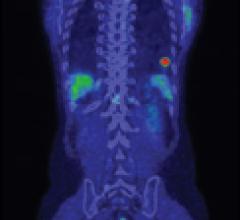

VIDEO: Use of Artificial Intelligence in Nuclear Imaging